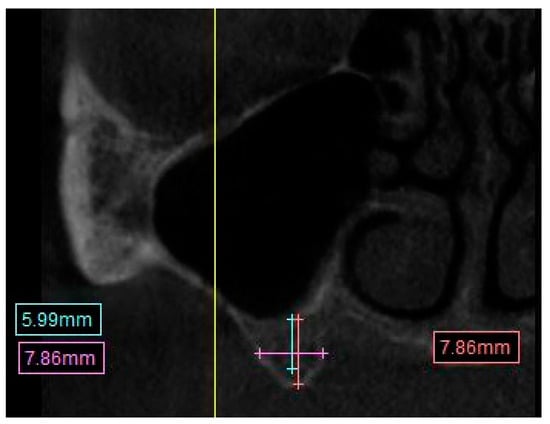

• Distance from the crest of maxillary ridge to the floor of the maxillary sinus (Figure 2).

A straight line from the crest of the planned molar location to the inferior border of the maxillary sinus.

Figure 2. CBCT image showing measurement calculation for the distance from maxillary ridge crest to the floor of the sinus.